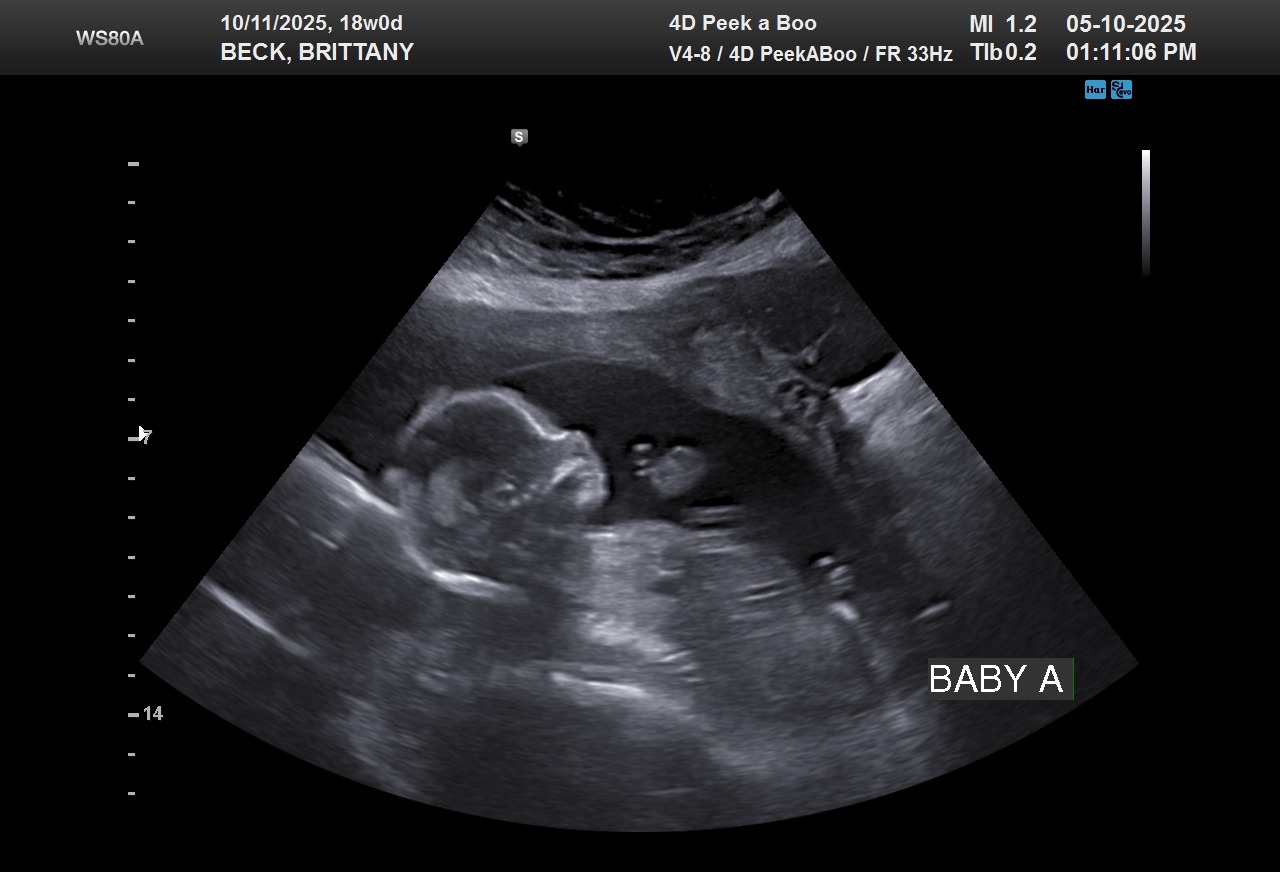

Brittany was recently diagnosed with Sjögren's Syndrome and hospitalized for the past week due to complications with baby A and her heart. Baby A has a complete heart block, with fluid around the heart and abdomen and does not have a good prognosis. Brittany will have to continue infusions, as well as numerous appointments 2+ times a week to monitor baby A's current condition with possible extensive medical travel in the future as things progress.